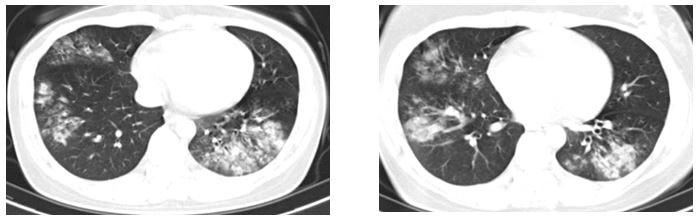

Xét nghiệm cho thấy chỉ số viêm tăng cao, phim chụp ngực ghi nhận thâm nhiễm viêm cả hai phổi. Người bệnh được điều trị kháng sinh đường tĩnh mạch tích cực, xét nghiệm loại trừ các nguyên nhân khác (lao, u phổi,…). Bệnh cải thiện, sức khỏe người bệnh ổn định và ra viện sau 10 ngày điều trị.

Viêm phổi là tình trạng nhiễm trùng xảy ra ở các phế nang, tiểu phế quản, phế quản tận,… Viêm phổi xảy ra ở ngoài cộng đồng dân cư được gọi là viêm phổi cộng đồng. Khi bị viêm phổi, trong các phế nang của người bệnh chứa đầy dịch viêm xuất tiết, gây ra các triệu chứng lâm sàng và biến đổi trên phim chụp ngực.

Triệu chứng đặc trưng thường là thâm nhiễm mới ở phổi trên phim chụp X-quang, cùng với một hoặc nhiều các triệu chứng sau: sốt, ớn lạnh, ho, có đờm, khó thở, chứng đau cơ, đau khớp, đau do viêm màng phổi.